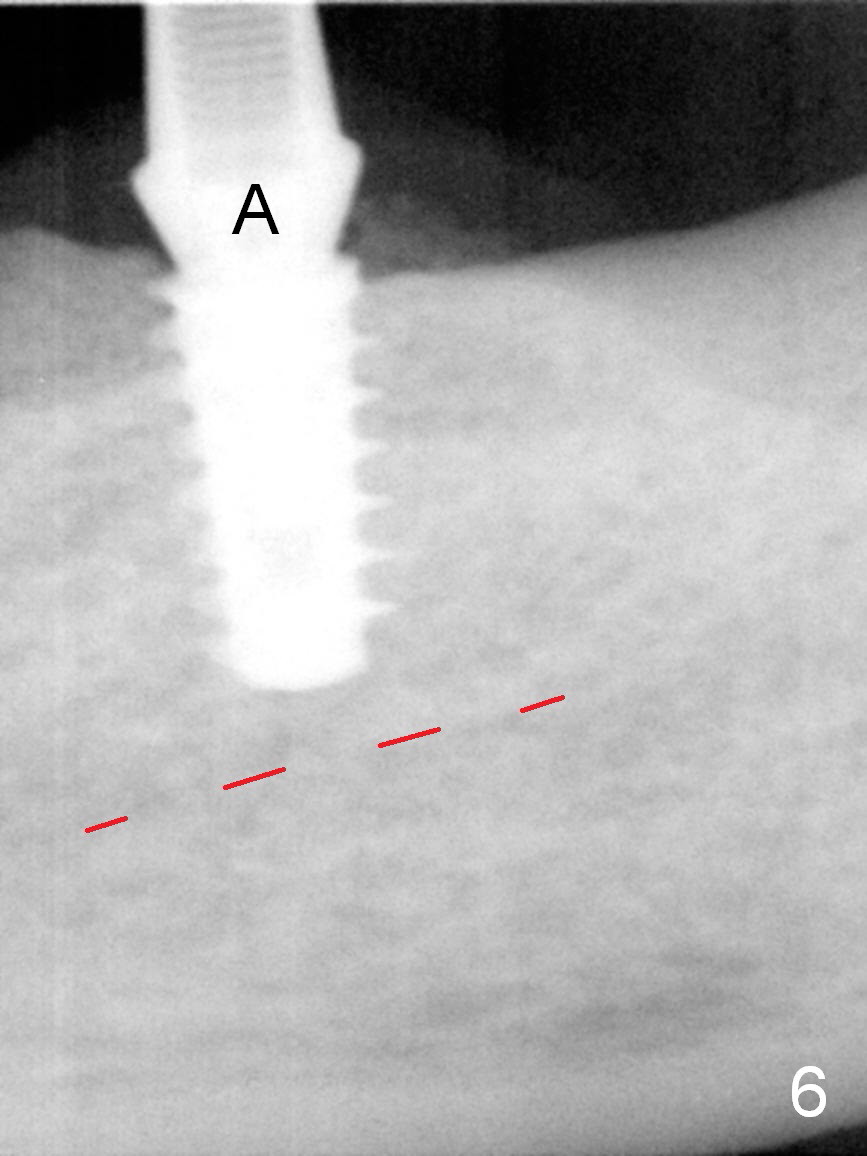

Except the tooth #30, the patient is completely edentulous (Fig.1,2). His chief complaint is "food gets into the missing tooth area". Due to short guide pin (Fig.3) and parallel pin (Fig.4), it is difficult to calculate precisely at the site of #19 the distance to the superior border of the Inferior Alveolar Canal (Fig.4 red dashed line). The clearance appears to be limited when a 4.3 mm drill is in place with 11 mm depth (Fig.5). Therefore an implant shorter than the last drill is placed (5x9 mm, Fig.6). Insertion torque is >50 Ncm. A 5x4(2) mm pair abutment is inserted temporarily to check occlusion with the opposing dentition (A). Finally a 5x2 mm healing abutment is placed with harvested autogenous bone placed between the implant and abutment (Fig.7). Before discharging the patient, the lower RPD is in place to check the position of the implant/abutment (Fig.8).